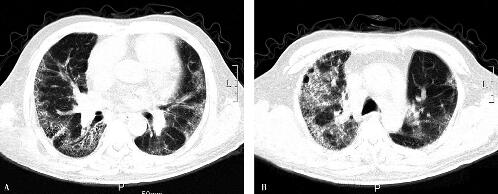

7.胸部CT:双肺野弥漫性条索状、斑片状阴影及磨玻璃影,以肺周边部为主,近胸膜处可见纤维网格影,以双下肺为著,与2011年1月2日胸部CT比较无明显吸收。心包积液,双侧胸膜增厚(图2)。

图2